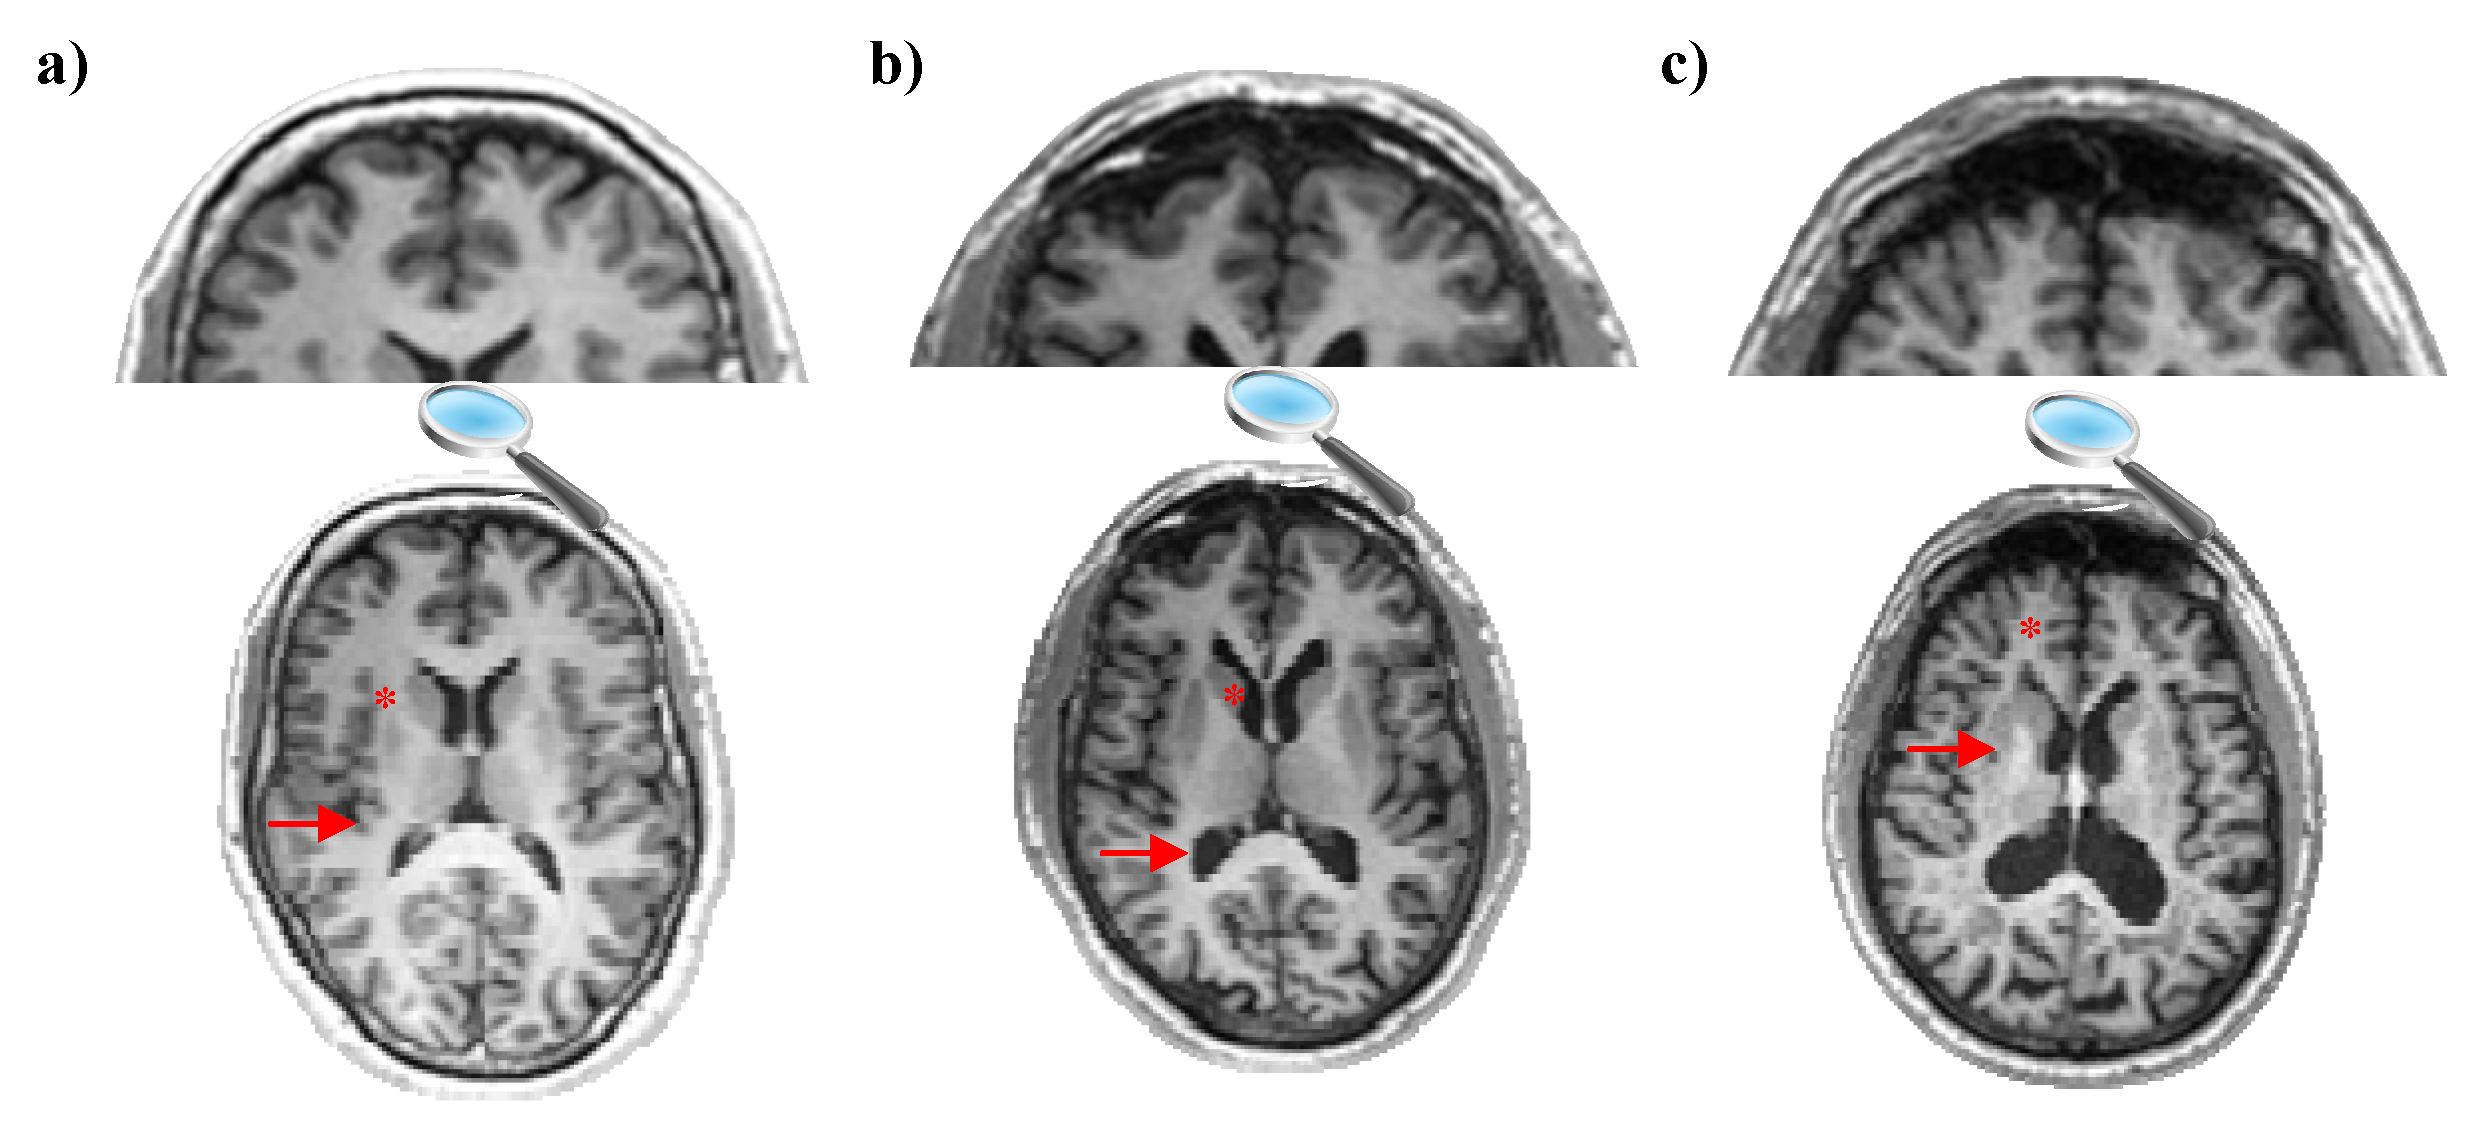

3.1. Tensor-Based Morphometry

- It can precisely and quantitatively measure the shape and size properties of brain structures with TBM.

- It can compress and reduce the data volume in brain images. This can help with faster data processing.

- It can be used to compare structural changes between different individuals, groups, or time points.

- TBM has the ability to make statistical analyses of brain structures.